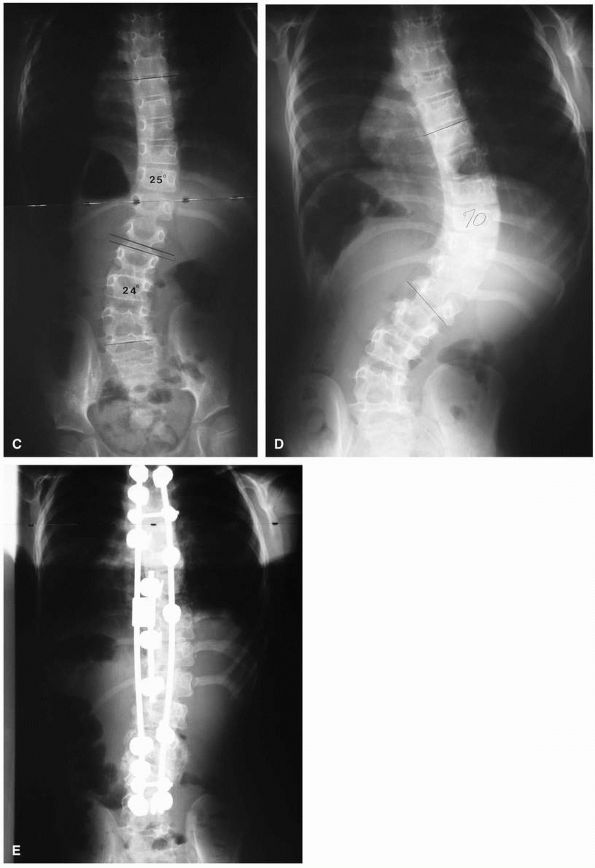

![]() |

FIGURE 16-9. (A) Juvenile idiopathic scoliosis in a 7½-year-old boy with an 80° thoracic curve that progressed despite bracing. (B)

Same patient at age 8 years and 11 months. Curve is maintained at 41° with distraction instrumentation and fusion at hook sites. Patient is wearing TLSO external support. Definite surgery is planned at puberty. (C) A 7½-year-old girl with juvenile onset scoliosis; she was initially treated in a brace but her curve progressed (D), necessitating anterior and posterior fusion (E). |

FIGURE 16-9. (Continued)